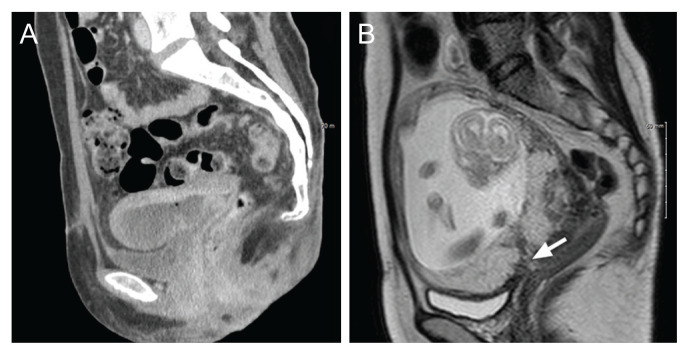

Abstract Image

In an 8-year period at two medical center, 138 patients underwent uterine artery embolization, and 11 of them were diagnosed with uterine necrosis. Among them, three were successfully conceived. However, one of them developed an arteriovenous malformation after an artificial abortion, and another experienced complications, including placenta previa and placenta accreta spectrum, which resulted in early preterm delivery and recurrent postpartum hemorrhage, necessitating subtotal hysterectomy. Therefore, it is crucial to prepare for potential adverse pregnancy outcomes in subsequent pregnancies for patients with a history of uterine necrosis.